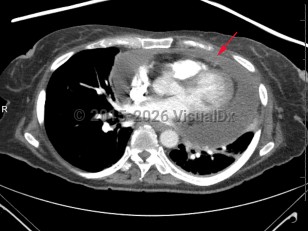

Cardiac tamponadeCardiac tamponade

PericarditisPericarditis